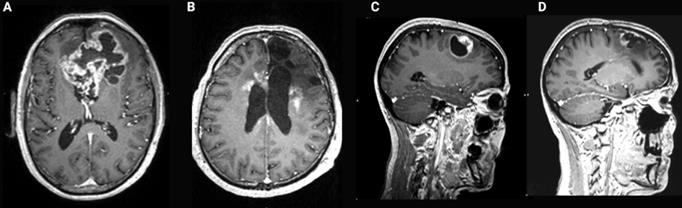

Figure 8

Contrast-enhanced T1-weighted brain magnetic resonance imaging (MRI) of glioblastoma (GB). (A) Common presentation of bulky bifrontal GB with irregular (nodular) contrast enhancement surrounding central tumor necrosis. (B) Illustration of radiation necrosis appearing as multiple foci of pathological contrast enhancement, periventricular in the left and right frontal lobe as well as anteriorly and posteriorly in the corpus callosum. (C) Nodular contrast-enhancement in a GB tumor on T1-weighted brain MRI pre-resection. (D) New irregular contrast-enhancement at the resection cavity at 1 year after a complete surgical resection reflecting tumor recurrence or treatment-related changes which have a similar appearance on MRI [31].